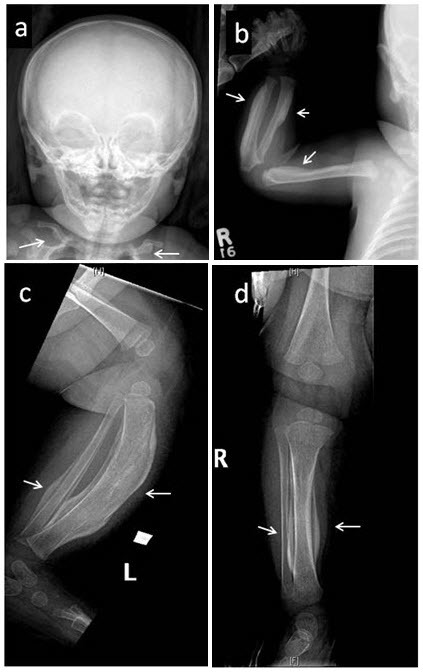

卡菲病,也叫婴儿骨皮质增生症,是一种常见于婴儿的骨病。卡菲病的主要特征是新生骨过度产生。骨骼异常主要影响颚骨、肩胛骨、锁骨、手臂和腿的长骨骨干。病变骨的宽度可以增加至原来的两到三倍,这可以通过x射线成像看到。在某些情况下,彼此相邻的两个骨病变,如两个相邻肋骨或前臂相邻的长骨(桡、尺骨)或小腿相邻长骨(胫、腓骨)融合在一起。卡菲疾病的患儿也可有关节和肌肉等软组织疼痛、红肿。患病的婴幼儿还可能发热、烦躁。 卡菲病的症状和体征通常在患儿5个月前出现。在极少数情况下,骨骼畸形在出生前几个星期内发生,可以通过超声影像检查发现。产前致死性皮质醇增多是一种更为严重的疾病,可导致新生儿在出生前或出生后不久死亡,有时也被称为产前致死性卡菲病,但通常被看作一个独立的疾病。 卡菲病相关的肿胀和疼痛症状通常在几个月内缓解,原因尚不明确。通过正常的骨重建过程,过量的骨通常在患者2岁之前溶解吸收并被新生骨取代, x射线图像上检测不到病症。然而,如果是关节处两个相邻的骨发生融合,则很可能不会自然溶解吸收,因此会导致相关症状。例如,肋骨融合可导致脊柱侧凸、或胸廓活动受限,导致呼吸问题。 大多数卡菲病患者度过幼儿期后没有进一步的症状,偶见骨质增生于数年后再次复发。此外,一些曾在婴儿期患卡菲病的人成年后伴有其他骨骼系统或结缔组织病变,骨骼与结缔组织维持身体强度和柔韧性,受影响的患者会出现关节松弛,皮肤弹性增加或疝。